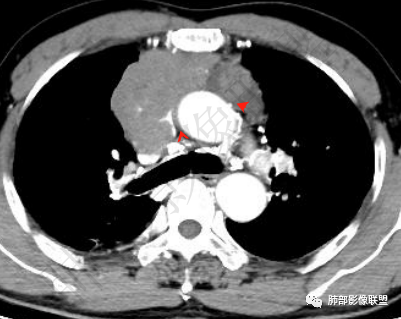

▲上腔静脉内瘤栓

▲病灶骑跨在主动脉前缘,主动脉包绕

▲左侧边缘有强化的病灶,似乎符合坏死或囊变、或有粘液类物质。内部似有裂隙、坏死。坏死边界偏清。

病灶边界不清,轻度分叶,后方部分紧密包绕升主动脉且侵入上腔静脉及左无名静脉末端,相应上腔静脉及左无名静脉管壁不完整。

面部肿胀(腔静脉阻塞综合征),前纵隔实性肿块,密度均匀,分叶,病灶内多个低密度区,与腔静脉分界不清晰,增强病灶轻度强化,肺门,纵膈淋巴结增大,胸腺癌?

晨读:男,60岁,颜面部肿胀1月入院。CT示右肺上叶条索影及实变影伴局部支气管扩张,肺大泡(陈旧性肺结核?)。前纵隔可见实性肿块,骑跨主动脉生长,平扫密度不均匀,内部可见低密度区,增强扫描渐进性不均匀强化,可见坏死区,上腔静脉受侵,考虑为恶性,侵袭性胸腺瘤或胸腺癌>淋巴瘤

晨读病例:男性患者,60岁,面部肿胀一月入院,影像表现,前纵隔实性肿块影,密度均匀,部分层面与腔静脉分界欠清晰,增强扫描病灶轻度强化,病灶内可见低密度无强化区,上腔静脉受侵犯,右侧肺门,纵膈淋巴结增大,考虑恶性病变,胸腺癌>侵袭性胸腺瘤,鉴别淋巴瘤。